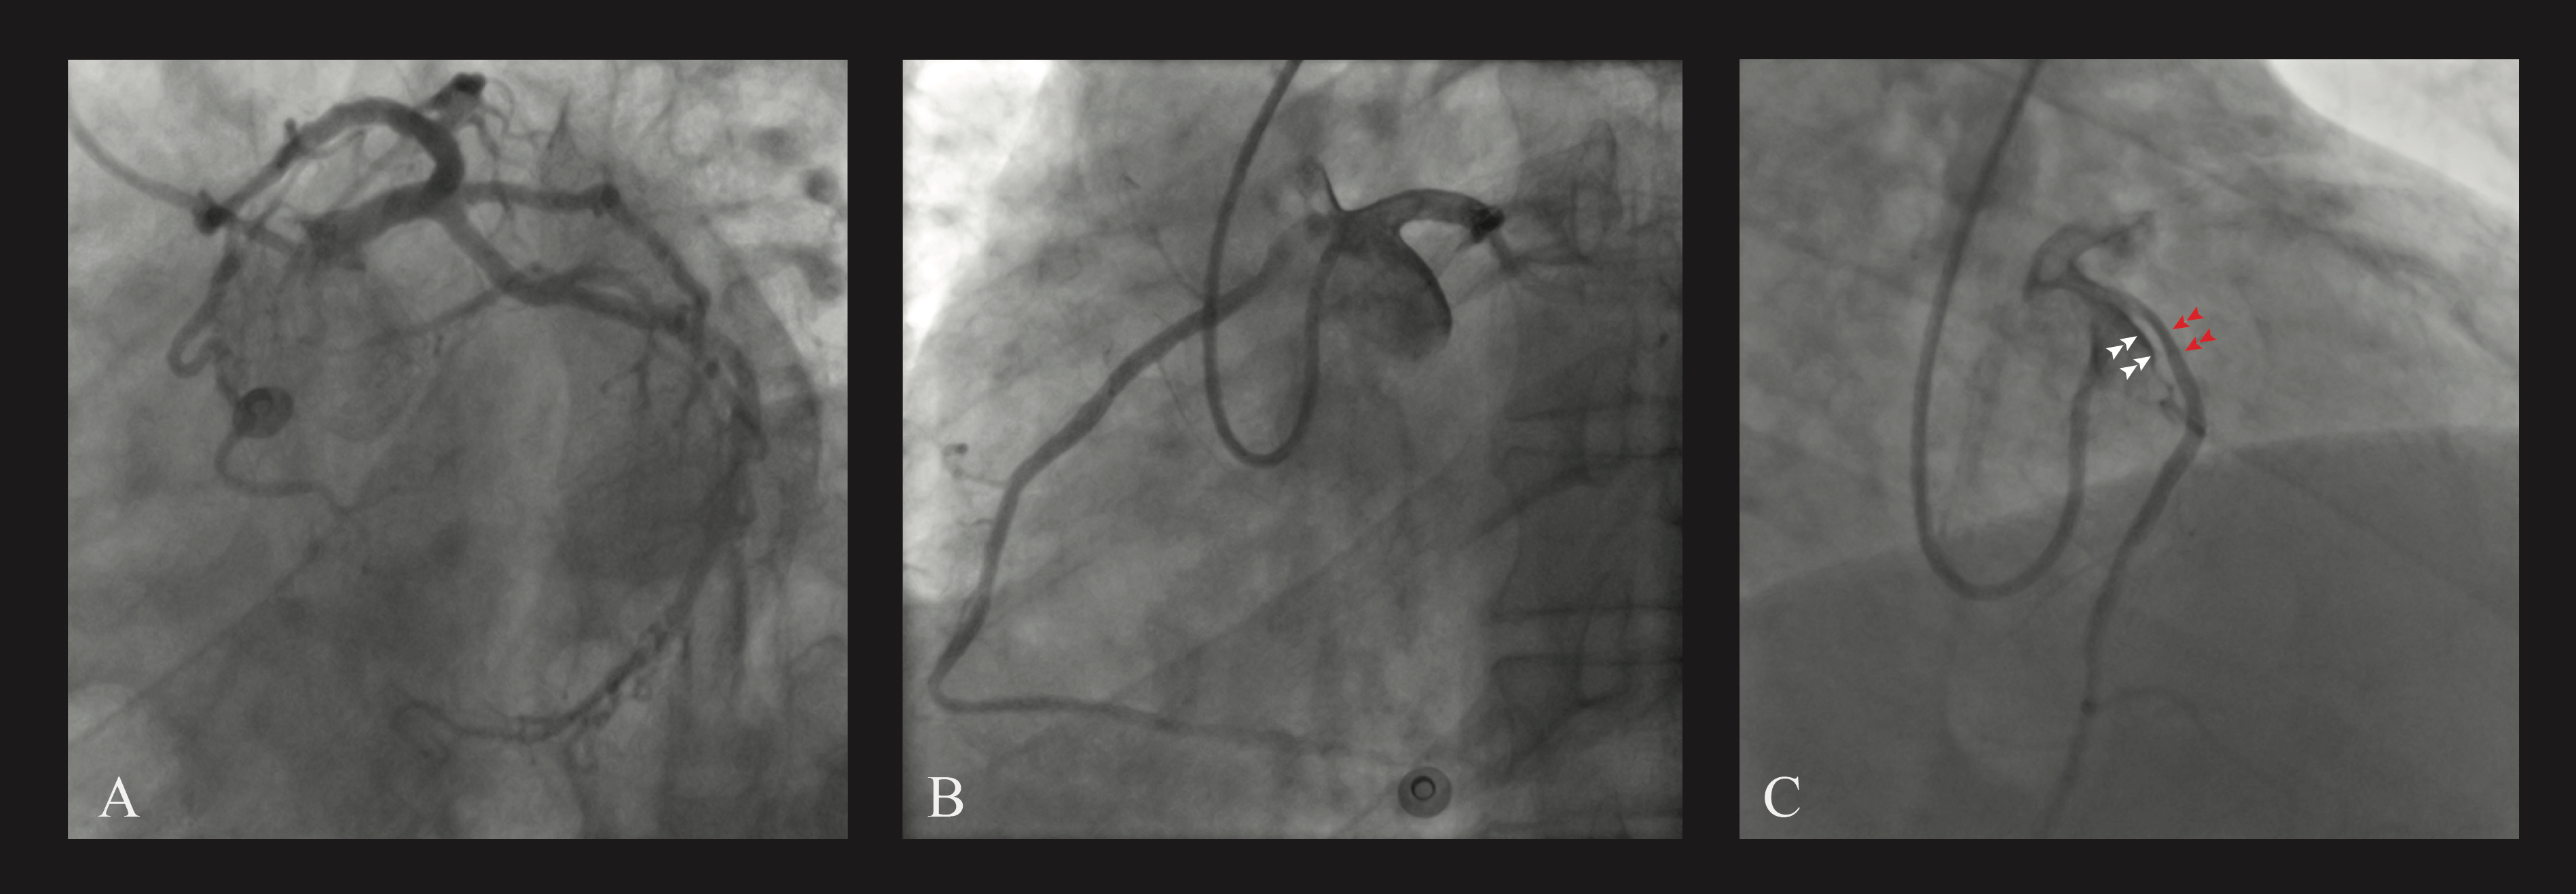

A 3.5 x 26-mm drug-eluting stent was implanted and post-dilated in the intramural RCA with a good result (Figure 3). The clinical course was uneventful. After 12 months, the patient was asymptomatic and coronary computed tomography confirmed the good patency of the implanted stent (Figure 4).